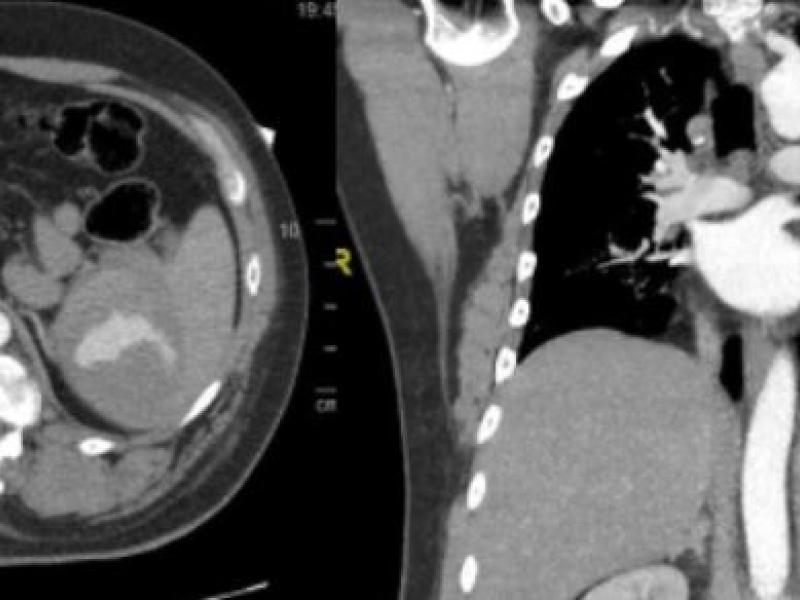

EM Daily What's the Diagnosis? By Dr. Abby Renko January 12 2022 A 47 yo M presents to the ED after being struck by a vehicle